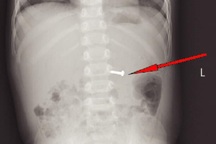

Bác sĩ phát hiện dị vật kim loại trong dạ dày của bé (Ảnh: Bệnh viện cung cấp).

Tại bệnh viện, kết quả chụp X-quang cho thấy có hình ảnh dị vật kim khí nằm ở vị trí trung tâm ổ bụng. Các bác sĩ chỉ định gây mê nội soi tiêu hóa cấp cứu gắp dị vật cho bé.